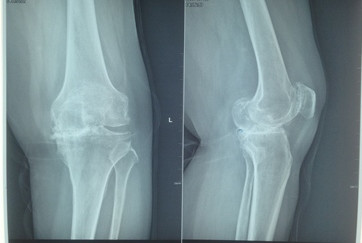

患者王某,女,54岁,合阳县人。二十余年前,出现左膝关节疼痛、肿胀,严重影响日常活动,稍微休息后感到缓解,但疼痛的症状时常发作,而且越来越重。为明确病情前来我院,在门诊检查后,诊断为膝关节骨性关节炎,由骨二科收住院。

患者曾在2015年因右膝关节重度骨性关节炎,在西安行右全膝关节置换术。住入我院后,骨二科副主任医师胡洪波为患者做了详细全面的检查,最终诊断为左膝关节骨性关节炎IV期,右全膝关节置换术后,高血压病3级。因为患者左膝关节的疼痛,导致走路不稳,影响到了日常生活,已经达到了手术指征,骨二科医师在经过和患者及家属的反复沟通后,决定为患者实施左侧全膝关节表面置换术。